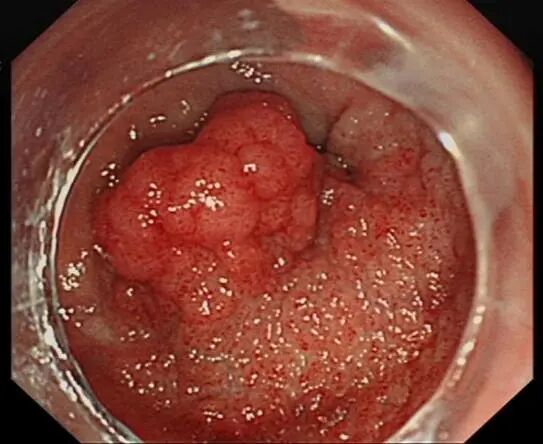

近日,患者温大爷因反复无痛性便血伴肛门肿物脱出半年就诊外院,行结肠镜检查发现其直肠距肛门4cm以上可见环周2/3生长的形状不规则新生物,大小约11cm*8cm,立即行活检病理回报管状-绒毛状腺瘤伴有高级别上皮内瘤变,此属癌前病变,应尽快切除。

在为温大爷完善了增强MR检查后,对温大爷的病情细致分析。认为肿瘤面积大,如果使用普通的内镜下息肉切除术,很可能无法清除彻底,留下复发的祸根;另外肿瘤离肛门比较近,如果采取传统外科手术,需切除部分肠段,后期可能存在肠瘘、出血、肠道狭窄,梗阻等风险,不仅无法保住肛门,且不利于术后恢复,以后生活质量会大大下降,温大爷需要承受更多的痛苦。

根据温大爷的病情,结合各项辅助检查,温大爷转诊至赣州市第五人民医院肝病科消化肝病区行“内镜下粘膜下剥离术(简称ESD)”,不开刀清除“肿瘤”。